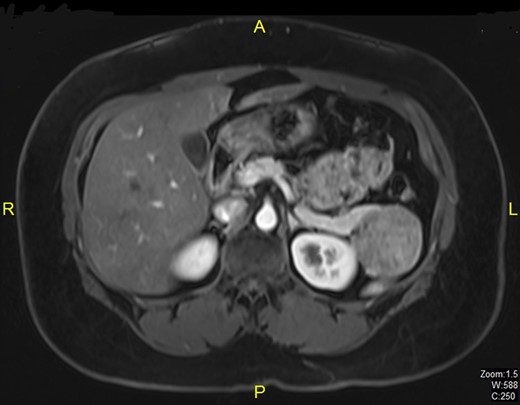

A 38-year-old married woman, who had undergone brachytherapy, radiotherapy and chemotherapy for cervical cancer in the Philippines in the year 2011, was admitted to our hospital after a follow-up CT scan of the abdomen in 2012 revealed a lesion in the tail of pancreas which on subsequent MRI scan was diagnosed as benign intraductal papillary mucinous neoplasm measuring 5.1 × 4.6 cm (Fig. 1). Physical examination revealed no abnormal findings. Tumor markers including CA 19-9 and CA 125 were within normal limits. Cervical smear was negative for malignancy. The patient underwent distal pancreatectomy and splenectomy. Histopathological examination showed solid pseudopapillary tumor of the pancreas (Fig. 2). Postoperatively she developed unilateral lower lobe consolidation. She recovered smoothly and was discharged 8 days after resection.

A higher power picture shows the pseudopapillae are lined by layers of bland cells and the nuclei are oval with finely stippled chromatin, nuclear grooves and indistinct nucleoli (H&E ×60).